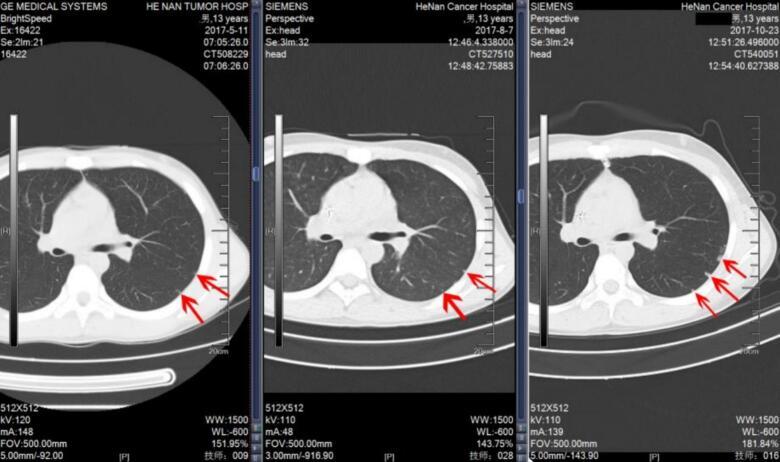

We retrospectively analyzed clinical data from 126 osteosarcoma patients aged 20 years or younger who were treated at Henan Cancer Hospital between January 2012 and January 2022. Pre-treatment thin-slice computed tomography (CT) scans of lung were used to categorize patients into three groups: no IPN (n = 100), solitary IPN (n = 16), and multiple IPNs (n = 10). Baseline characteristics, primary tumor parameters, treatment modalities, and follow-up data were collected. Univariate and multivariate analyses were conducted to assess risk factors and survival outcomes.

我们回顾性分析了2012年1月至2022年1月在河南省肿瘤医院接受治疗的126例20岁及以下骨肉瘤患者的临床资料。使用治疗前肺部薄层计算机断层扫描(CT)将患者分为三组:无IPN(n = 100)、孤立性IPN(n = 16)和多发性IPN(n = 10)。收集基线特征、原发肿瘤参数、治疗方式和随访数据。进行单因素和多因素分析以评估危险因素和生存结果。